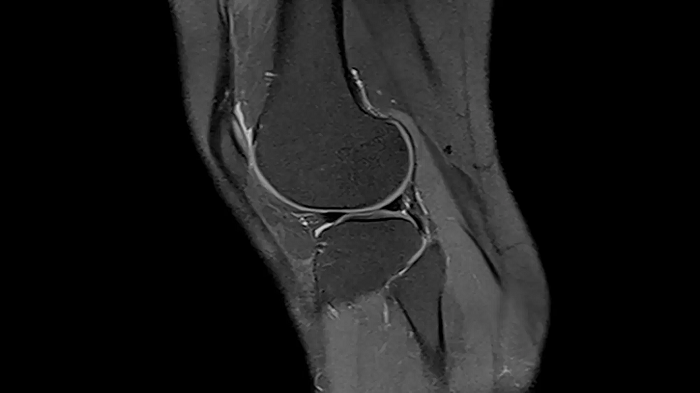

Knee

PD TSE FatSat with SMS

In MSK imaging, TSE is the workhorse. Using the Siemens Healthineers dedicated SMS TSE technique, users can stay on top of measurement times without compromising on image quality while resolving orthopedic clinical concerns.

TA = 3:46 minutes

Image Courtesy: University Hospital Erlangen, Germany | Image-ID: 4aaaa0449